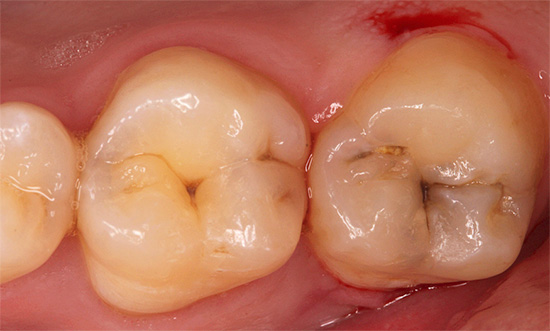

Un aspetto tipico dei denti con carie cronica è mostrato nella foto qui sotto:

Non ci sono lesioni estese dei denti e in alcuni punti le aree scure sono di dimensioni molto ridotte e spesso non attirano l'attenzione del paziente. Di solito il dolore è assente.

- La carie cronica profonda differisce dalla media solo per la profondità della cavità. Inoltre non ha bordi a smalto sporgenti, generalmente ben lucidati.

In tutte le fasi dello sviluppo della carie, toccare l'area interessata non provoca dolore. La percussione provoca dolore di passaggio rapido solo in caso di complicazioni sotto forma di pulpite o parodontite.